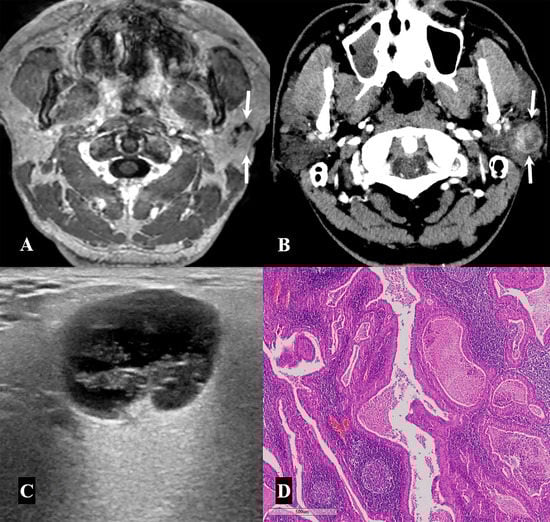

| Reactive lymph node | 11/49 (22.5%) |